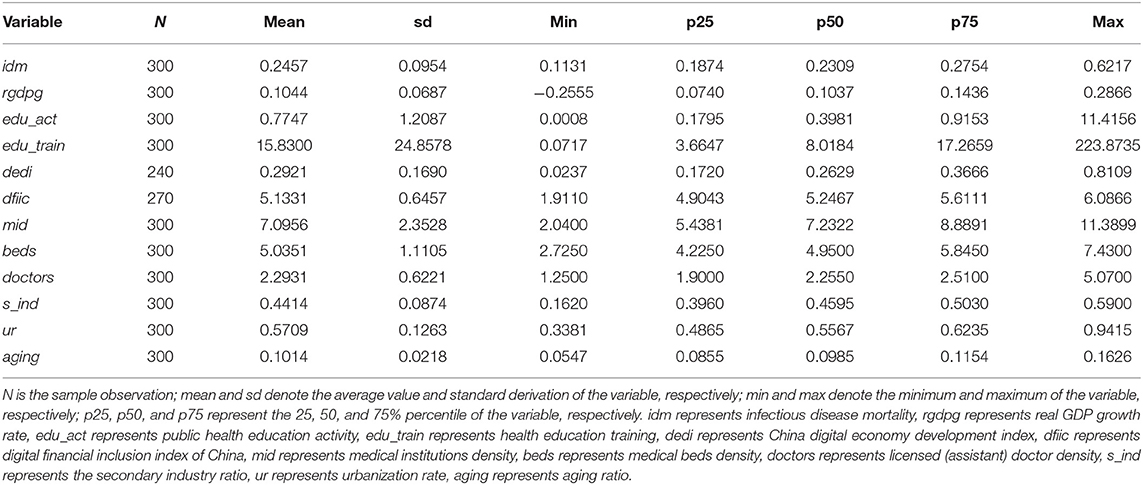

Treatment of Budd-Chiari syndrome with inferior vena cava, PDF) Racial and Ethnic Disparities in the Impact of Obesity,

PDF) Racial and Ethnic Disparities in the Impact of Obesity, PDF) Preparation of Immunotoxin Herceptin-Botulinum and,

PDF) Preparation of Immunotoxin Herceptin-Botulinum and, Frontiers | Business Cycle and Public Health: The Moderatingアーカー18Kイエローゴールド/ダイヤジェルム リング#ピンキーリング#ダイヤモンド名前の「ジェルム」はフランス語で「芽、発芽」。サイズがわかりかねますが、当方細身で薬指だと7号です。右小指でジャストサイズでした。名古屋高島屋#AHKAH にて購入状態はお写真にてご確認ください。10回程の着用だったと思います。※ご購入前にコメントください☆定価49,500円消費税込AB1726010200#一粒ダイヤ

Frontiers | Business Cycle and Public Health: The Moderatingアーカー18Kイエローゴールド/ダイヤジェルム リング#ピンキーリング#ダイヤモンド名前の「ジェルム」はフランス語で「芽、発芽」。サイズがわかりかねますが、当方細身で薬指だと7号です。右小指でジャストサイズでした。名古屋高島屋#AHKAH にて購入状態はお写真にてご確認ください。10回程の着用だったと思います。※ご購入前にコメントください☆定価49,500円消費税込AB1726010200#一粒ダイヤ